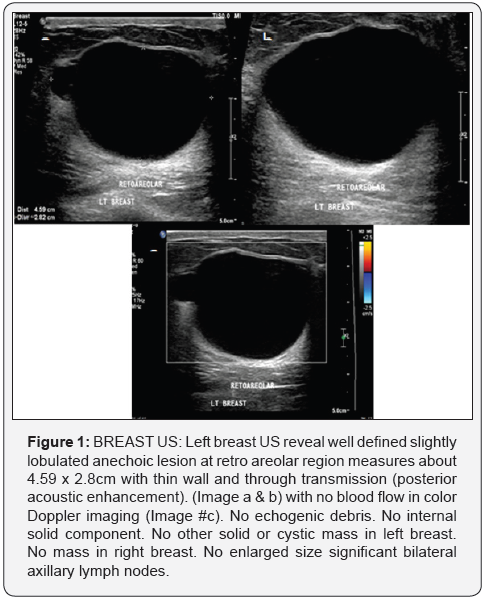

(Figure 1) Case Detail and Cytology Report from Cerner

Breast cysts are the commonest cause of breast lumps in women between 35 and 50 years of age [1,2]. A cyst occurs when fluid accumulates due to obstruction of the extralobular terminal ducts, either due to fibrosis or because of intraductal epithelial proliferation. A cyst is seen on USG as a well-defined, round or oval, anechoic structure with a thin wall and smaller cyst are compressible and larger cyst are usually mildly compressible and color Doppler demonstrates no flow (shown in this case).